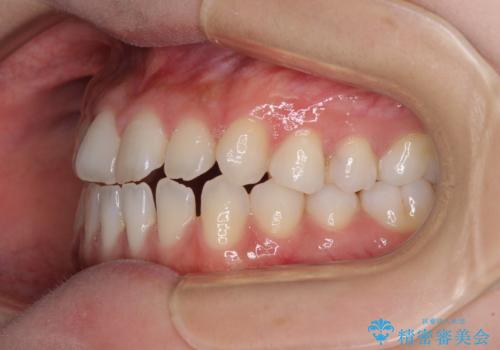

舌突出癖で口元が開いてしまう 舌トレーニングを行ったインビザライン矯正

- 前歯の上下スペースと前歯の隙間を気にして来院された患者様です。

インビザラインにより上下の前歯の隙間を閉じていくこととしました。

上下の隙間に舌が入り込むことが、すきっ歯やオープンバイトの原因であったため、舌の筋肉のトレーニングも並行して行い、後戻りの抑制を図りました。